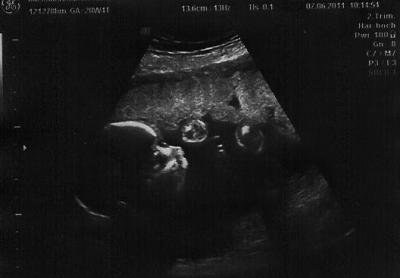

Hallo Mädels.... Melde mich zwar hier selten zu Wort,aber muss das doch auch mal los werden. Urin i.o., 6kg seit anfang der Ss zugenommen, TG zeigt keine Wehentätigkeit. So nun zum Würmchen,ihm geht es ausgesprochen gut nach Berechnung der FL- Länge ist es ca 25 cm und 406gr. schwer. Sehr Bewegungsfreudig heute,zumal die letzten Tage im Bauchhaus sehr ruhig waren. Achso leider noch kein Outing möglich, weil es zu zappelig war. Nun hoffe ich ja auf die FD am Donnerstag,mal schauen was wird ich drücke mir schon selber die Daumen. So hier noch ein Us- Bild was meine FÄ gerade in einem ruhigen moment erhaschen konnte. Lg Marion

Bild zu Gerade von der Vu rein... - Forum für Oktober - Mamis